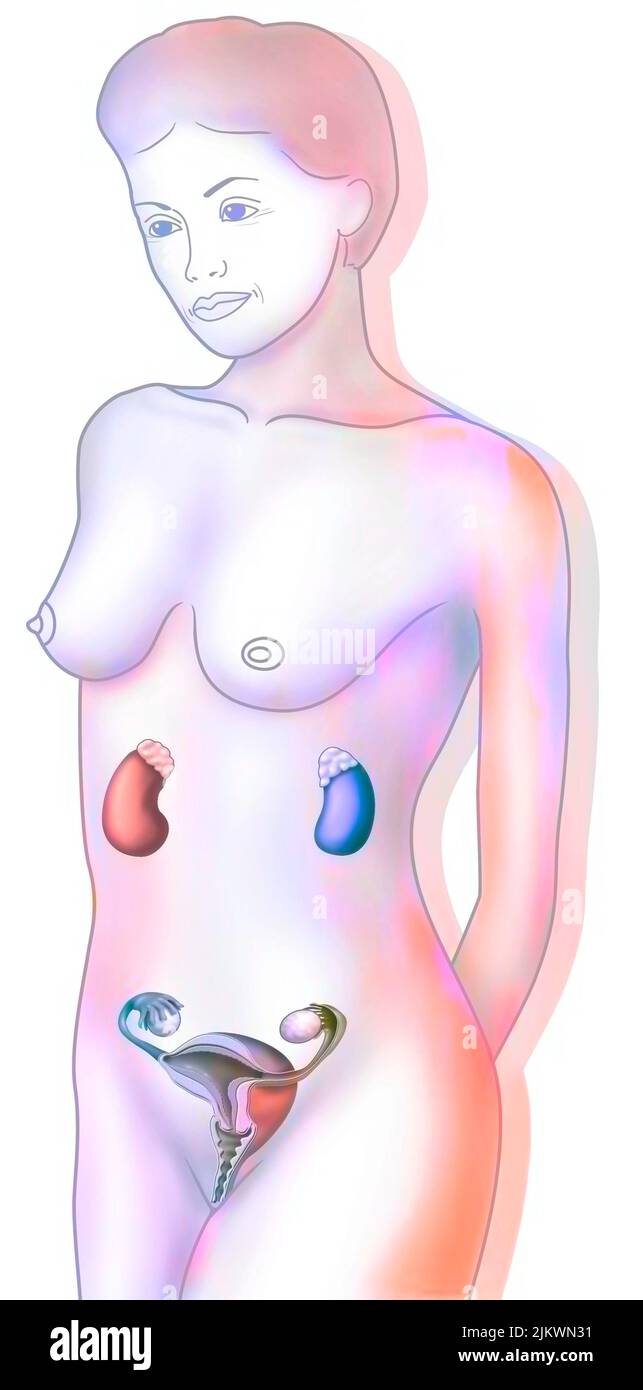

RF2JKWRM1–Vue antérieure des organes génitaux féminins avec vagin, utérus, trompes de Fallope, ovaires.